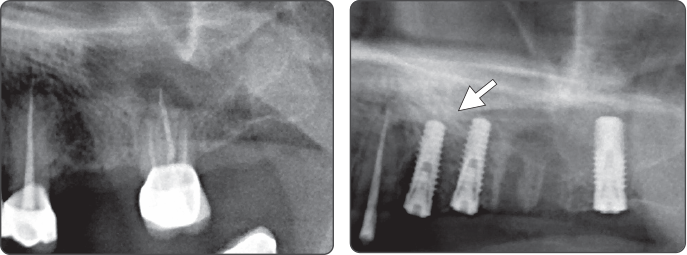

Secuencia-expansor

▶ Immediate Implantation and Sinus Lift Technique with Tap Drill (Ø4.0 Fixture)